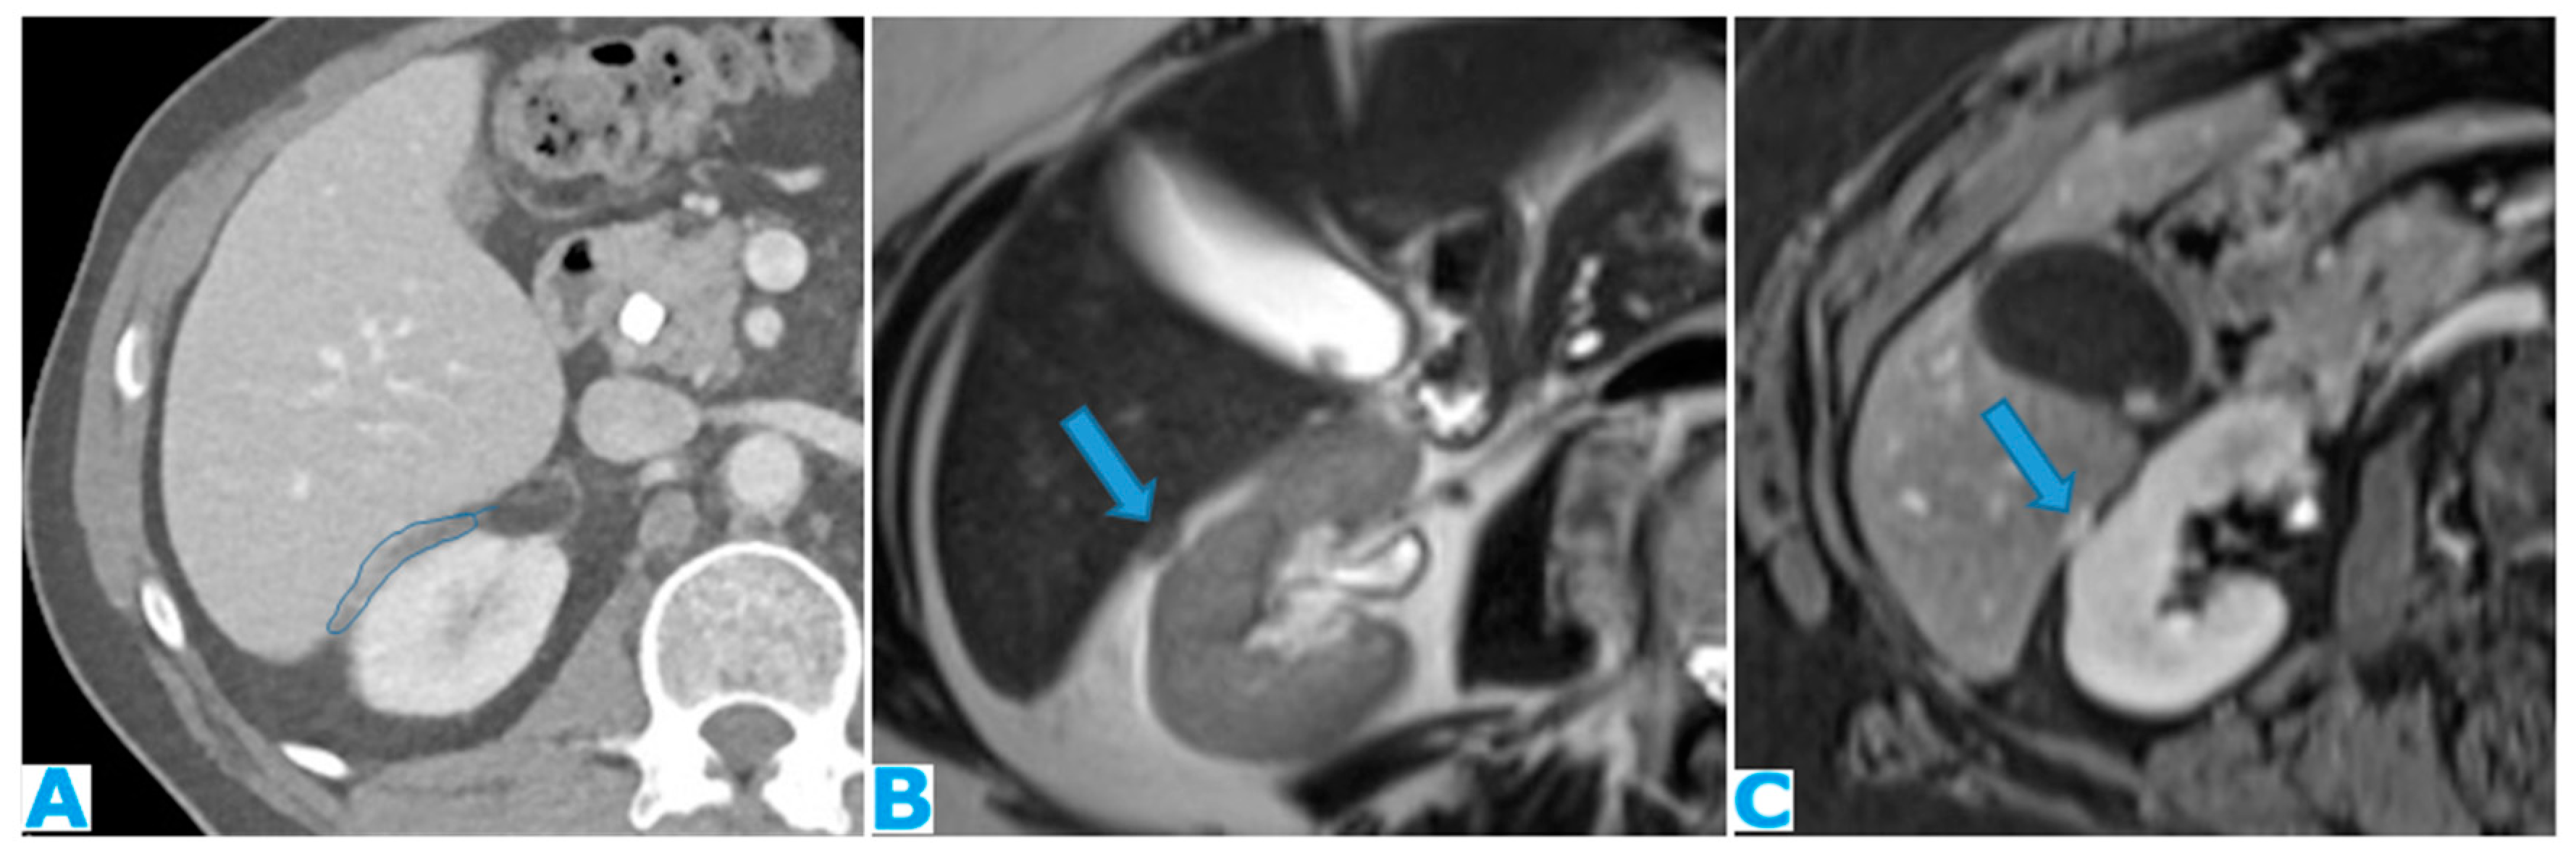

Figure 24.

Axial CE-CT (A), axial T2WI (B), axial CE portal phase FS T1WI (C). PC from endometrial carcinoma: Deposit seeding within the mesenteric leaves.